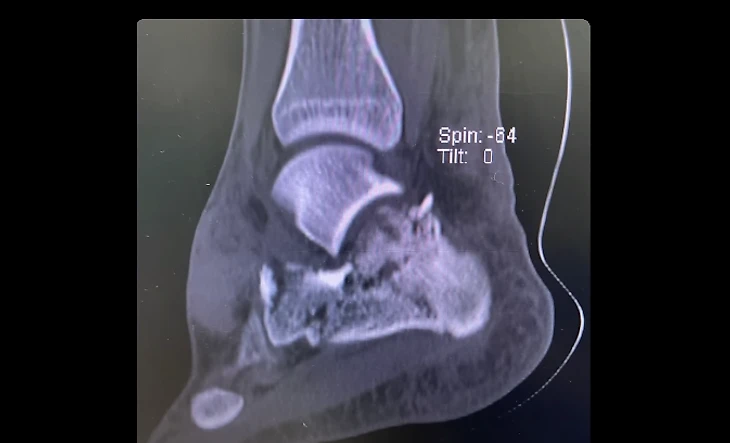

И с другого ракурса:

Да, заезд «Ф-2» в Джидде пошел совсем не по плану: раздробил пяточную кость, слег в больницу и пропустил финал сезона.

Однако самым опасным последствием аварии оказалось повреждение мозга – Энцо даже потребовалась операция!

А еще у меня вскрылось сильное кровотечение в мозгу. Когда его просканировали, мой мозг, оказывается, уже сдвинулся на 8 мм по отношению к центральной оси. Его вдавило в одну сторону [черепа]! А ведь после аварии обычно думаешь, что худшее позади.

Когда вот так достаешь кусок кости – он обратно не вырастает. Потому у меня здесь металлическая пластика.